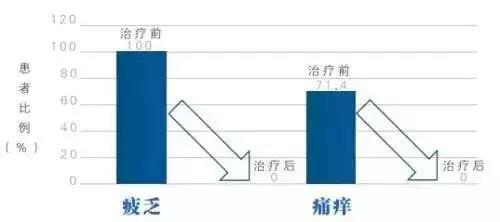

缓解病情症状

研究显示:干细胞治疗可显著改善肝病患者的疲劳与瘙痒症状,从而提高患者的生活质量。